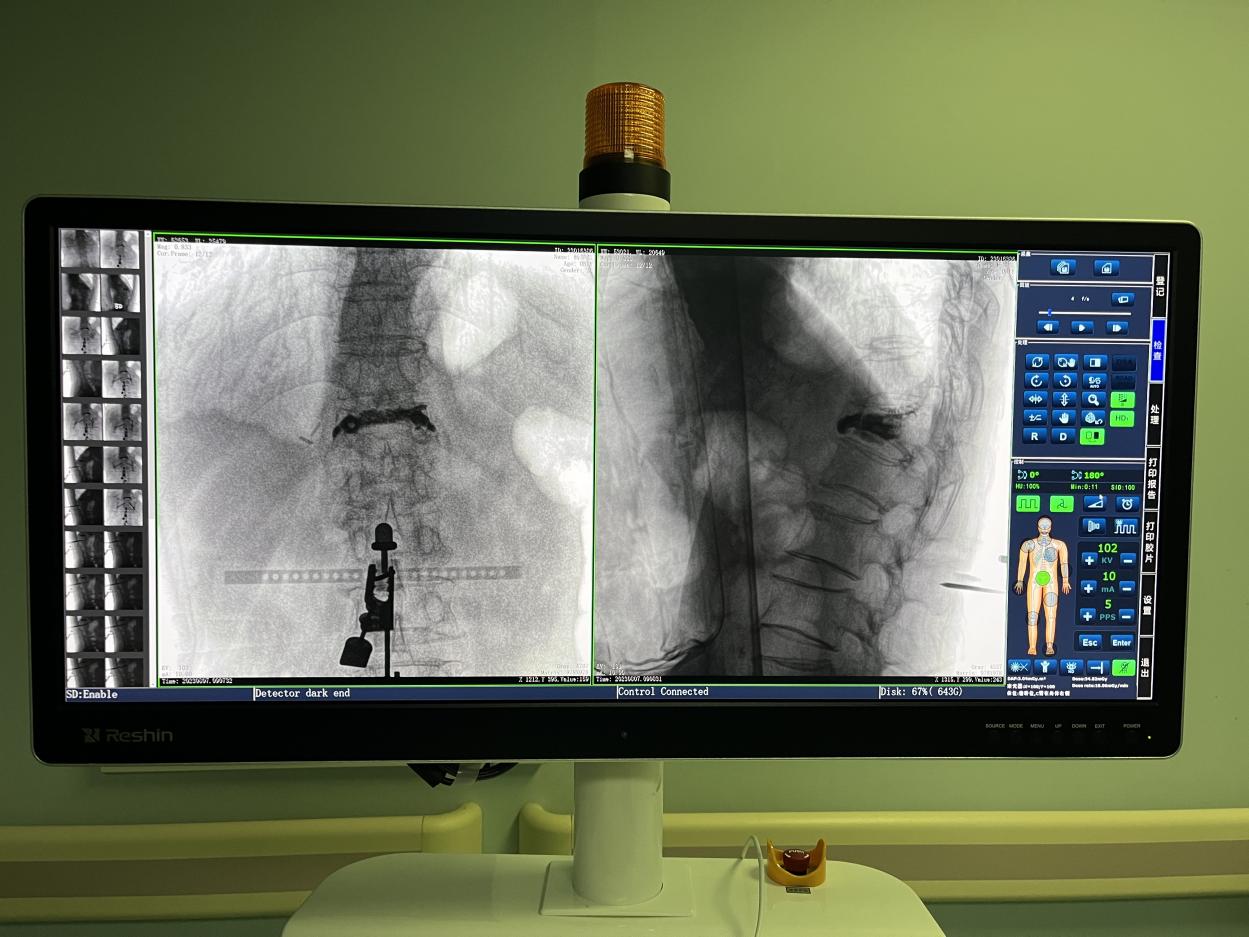

骨科機器人手術-術中影像

PL300B搭配普愛醫(yī)療自主研發(fā)生產(chǎn)的平板三維C形臂使用,通過三維立體術中圖像,手術醫(yī)生可從各個方位觀察合適的手術入路,并進行關鍵數(shù)據(jù)測量,從而最大限度地避開危險區(qū)。